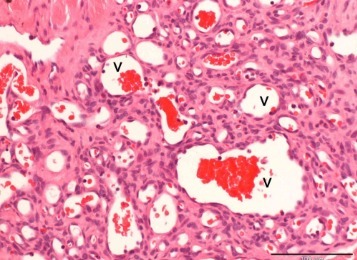

Producen cuadros febriles PEROOO acompañados de ANGIOMATOSIS

Nota: la angiomatosis es el crecimiento benigno de pequeños capilares ( es más usado en cortes histológicos)